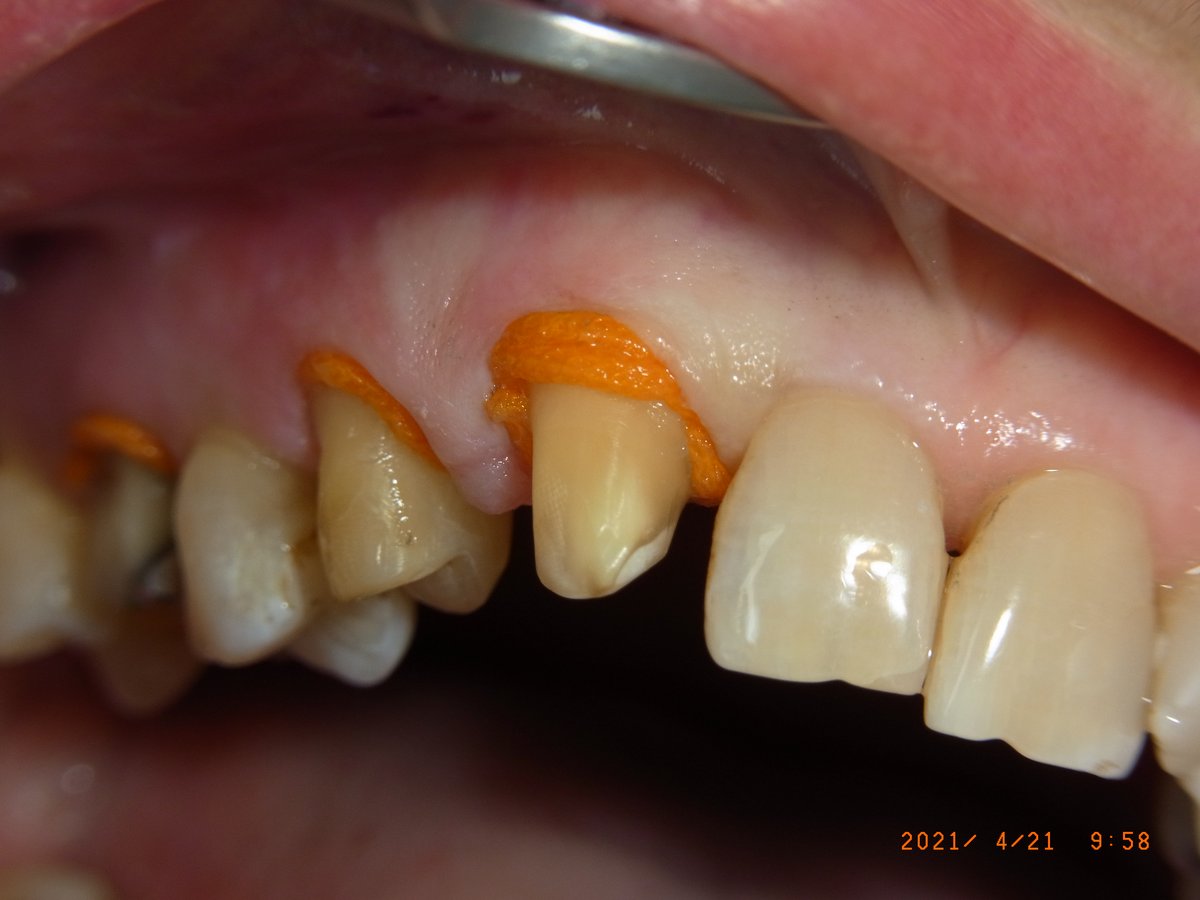

Gute Patienten- (durch Prophylaxe) und Sulcusvorbereitung (intragingivale, adrenalinhaltige Anästhesie, Faden Knit-Pak Gr. 2 (Fa. Premier) mit Racestyptine (Fa. Septodont), ca. 10 min Einwirkzeit) und möglichst knochentrockene Situation direkt vor der Abformung bleiben wichtig. (Anmerkung 7/2023: Die Abdruckspritze ist wieder dabei, weil sie die Luftblasen im Sulcus reduziert.)

Retraktionsfaden Knit-Pak Gr. 2 mit Racestyptine an den Frontzähnen des Oberkiefers: Der orange Faden öffnet den Sulcus für die anschließende Abformung.

Nahaufnahme: Der Faden liegt tief im Sulcus und verdrängt die Gingiva zuverlässig. Die knochentrockene Situation ist für eine fehlerfreie Sulcusabformung entscheidend.